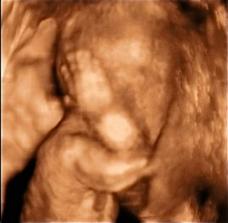

@erikababula čo reálnejšieho máte na mysli o bábätku v brušku,ak nie jeho 4D fotky? 🙂